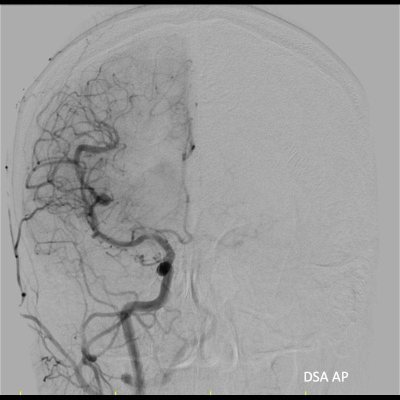

- G) AP, oblik ve lateral DSA görüntülerinde lezyon lokalizasyonunda MCA belirgin (oklar) görünümde olup erken venöz dolum izlenmedi.

- H) Lateral, ters oblik, oblik ve AP 3D DSA görüntülerinde dilate arteriyel vasküler anomali (oklar) izleniyor. Erken venöz dönüş yok.

- Olgumuzda vasküler anomali tanısı DSA ile konulmuştur.